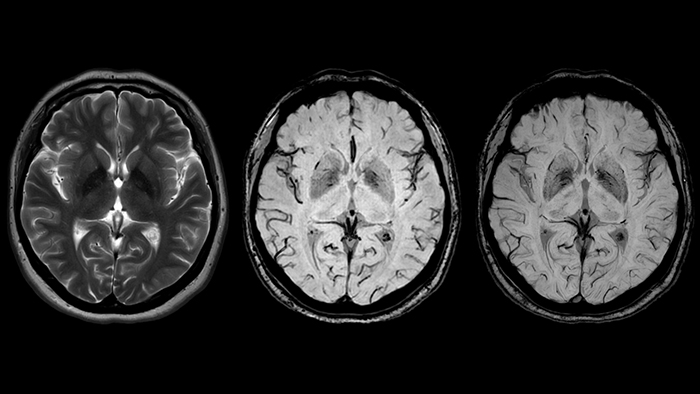

Идиопатическая болезнь Паркинсона (БП), вызванная прогрессивной потерей дофаминергических нейронов в черной субстанции головного мозга, является самым распространенным нейродегенеративным заболеванием. Нигросомы – небольшие группы дофаминергических клеток, в которых наиболее активно протекают процессы нейродегенерации. В диагностике особое внимание уделяется нигросоме-1, содержащей наибольшее количество дофаминергических нейронов. В норме на SWI изображениях она является гиперинтенсивной за счет низкого содержания в ней железа [23] - черная субстанция по форме напоминает хвост ласточки (рис.13, слева).

БП сопровождается накоплением железа в нигросоме-1 и снижением сигнала от этой области, “хвост ласточки” изменяется на “запятую” (рис.13, справа), что является маркером данного заболевания [24]. Недавнее исследование Zorzenon et al., использовавшее МР-томограф Achieva 3 Тл, с участием 62 пациентов и здоровых добровольцев показало эффективность использования этого маркера: чувствительность и специфичность составили 91% и 88% соответственно. Более того, значение коэффициента Каппа Коэна, который описывает соглашение между результатами различных экспертов, для SWIp выше, чем у T1- и Т2-взвешенных изображений. Норме соответствовал случай, когда отчетливо видна хотя бы одна из нигросом-1, положительный же диагноз ставился, если нигросома-1 не наблюдалась в одном или обоих полушариях [25]. В исследовании Zhao et al. [26] аналогичная методика использовалась для разделения пациентов с БП и сосудистым паркинсонизмом (СП). БП и СП имеют схожую клиническую картину, однако в силу различной скорости развития патологий для эффективной терапии необходимы маркеры, уникальные для одного из этих заболеваний [27]. Последовательность SWIp может стать одним из основных методов дифференциальной диагностики БП и СП. Так, в вышеупомянутой работе точность и специфичность определения БП по гипоинтенсивности нигросомы-1 (что соответствует отсутствию “хвоста ласточки”) составила 93% и 92%.